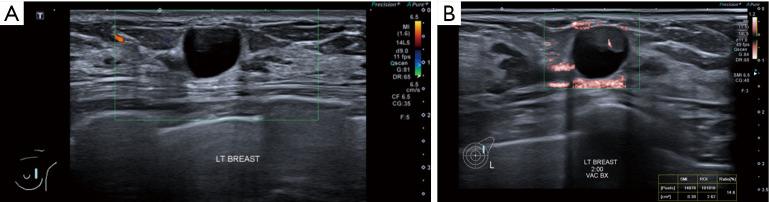

Several new ultrasound tools have been developed to further evaluate breast lesions detected on B-mode ultrasound. Strain elastography (SRE) was developed to assess the likelihood of malignancy of lesions based on their stiffness. This has been incorporated into the latest edition of the American College of Radiology (ACR) Breast Imaging Reporting and Data System (BI-RADS) lexicon and atlas. However, no agreed cut-off stiffness values have been established to distinguish benign from malignant lesions making the translation into routine clinical practice difficult. Superb microvascular imaging (SMI) was developed to better evaluate the vascularity within sonographic lesions and assess their likelihood of malignancy. However, there is also no agreed cut-off value for vascular index (VI) to distinguish between benign and malignant lesions. MicroPure was developed to better visualize and evaluate calcifications seen on ultrasound. Its effective use in breast screening and evaluating the calcifications detected for likelihood of malignancy have not been established. This article describes the original intended uses of these applications and reviews the studies evaluating them, showing the varying success of the translation of these tools into routine clinical practice. Also described are some other uses of these tools for which they were not originally intended. This illustrates the importance of being perceptive to alternative uses of imaging tools in their translation from bench to bedside.

已经开发了几种新的超声工具,以进一步评估在B型超声检查中发现的乳腺病变。应变弹性成像(SRE)是为了根据病变的硬度评估其恶性可能性而开发的。这已被纳入美国放射学会(ACR)乳腺影像报告和数据系统(BI-RADS)词汇表和图谱的最新版本。然而,尚未确定用于区分良性和恶性病变的一致的硬度临界值,这使得其难以转化为常规临床实践。超级微血管成像(SMI)是为了更好地评估超声病变内的血管情况并评估其恶性可能性而开发的。然而,对于区分良性和恶性病变的血管指数(VI)也没有一致的临界值。MicroPure是为了更好地显示和评估超声所见的钙化而开发的。其在乳腺筛查中的有效应用以及评估检测到的钙化的恶性可能性尚未得到证实。本文描述了这些应用的最初预期用途,并回顾了评估它们的研究,展示了这些工具转化为常规临床实践的不同成功程度。还描述了这些工具的一些并非最初预期的其他用途。这说明了在成像工具从实验室到临床的转化过程中,敏锐地感知其替代用途的重要性。